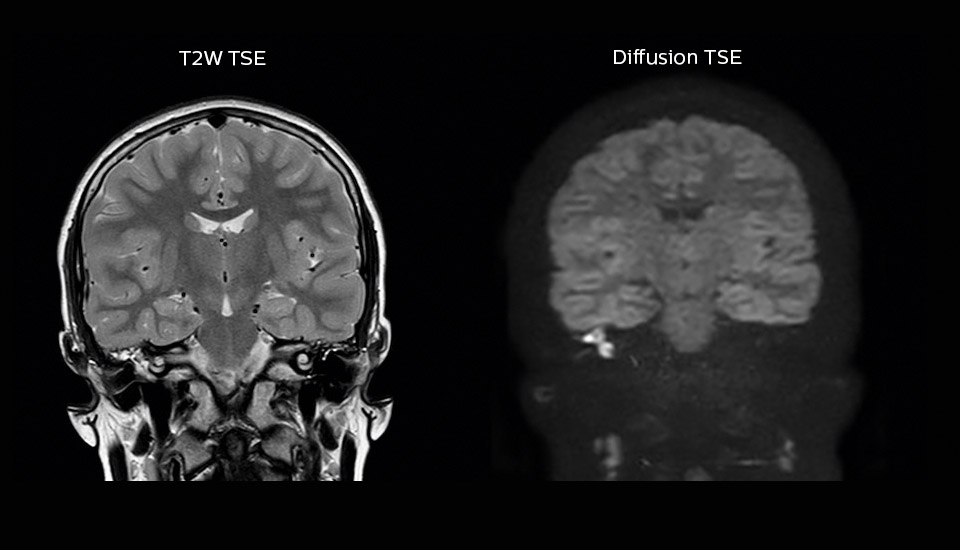

Excellent cholesteatoma imaging with Diffusion TSE

“Imaging cholesteatoma, benign tumors of the middle ear, has been a huge challenge,” says Dr. Heggelman. “We used to do CT, but then we were unsure if we were looking at an inflammation or a cholesteatoma. Also determining if residual cholesteatoma exist after surgery or visualizing recurrence used to be very difficult. Adding Diffusion TSE in our MRI protocol now effectively addresses this.”

“Diffusion TSE is far less sensitive to susceptibility differences than previously used EPI sequences. We appreciate the high resolution and the robustness of the sequence. The quality is so good that our confidence has increased. Also our ENT (ear, nose, throat) physicians are excited about the high resolution, the excellent lesion delineation and the sensitivity and specificity.”